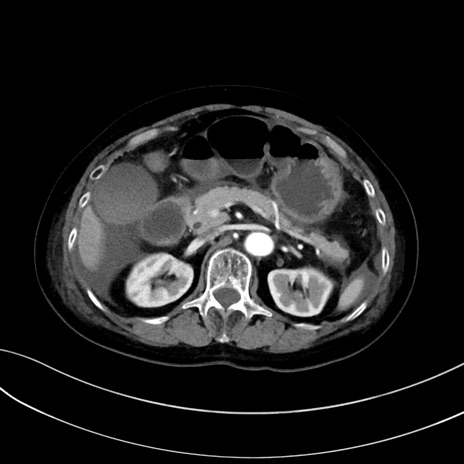

症例13 CT(横断像)1日半後